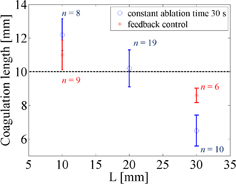

Standard image High-resolution imageOn the basis of these results, a prototype real-time feedback control system was constructed, and experiments using this system were conducted. The detection of the onset of coagulation is expected to be useful for exposure control in HIFU, and the real-time estimation of coagulation length in the US propagation direction is expected to be practically useful for lesion control in HIFU. Figure 12 shows LMI maps with real-time feedback control. During HIFU ablation, the tissue displacement could be measured. The results of the coagulation lengths after ablation with a constant ablation time of 30 s and feedback control based on real-time monitoring are shown in Fig. 13. The horizontal and vertical axes are the beam propagation distance and coagulation size measured with a ruler, respectively. The circles and asterisks in this figure indicate the results with constant ablation time and feedback, respectively. The dotted line indicates the targeted coagulation length. When the HIFU ablation time was constant, the coagulation lengths depended on the beam propagation distance (i.e., attenuation, and scatter). In contrast, when the HIFU ablation time was controlled by our system, the coagulation lengths were close to 10 mm. The average coagulation sizes and the average ablation times are shown in Table II. The size of the error for the short beam propagation distance (L = 10 mm) was reduced to 10% from 22%. The size of the error for the long beam propagation distance (L = 30 mm) was reduced to 14% from 35%. The standard deviations of the entire data set (calculated using the total of L = 10 and 30 mm) with constant time ablation and feedback control were 2.98 and 1.37, respectively. This result demonstrated that our prototype feedback control system could reduce the variation in coagulation size. In addition, the average ablation times for the short and long beam propagation distances were 25.2 and 35.2 s, respectively.

Standard image High-resolution imageFig. 13. Comparison between constant time ablation and feedback control.

Download figure:

In the case of a constant ablation time of 30 s, the coagulation size was approximately 10 mm for the US propagation distance of 20 mm. However, with the same ablation time, the coagulation size for the short propagation distance of 10 mm increased, which the coagulation size for the long propagation distance of 30 mm decreased. The cause of these results is the attenuation of US energy corresponding to the propagation distance. In actual treatment, the depth of tumor tissue and the acoustic properties of the US beam are different for each patient. Therefore, these variabilities in coagulation size can cause unnecessary damage to normal tissue and the risk of undertreatment for the entire tumor.

In contrast, with a feedback control system, the coagulation sizes were close to the targeted size of 10 mm for each propagation distance. The size errors in both cases are reduced to less than 15%. In the case of the short beam propagation, the estimated sizes of coagulations were larger than their target size. In the current experimental setup, it took 2 or 3 s to stop HIFU sonication after the estimated coagulation size reached 10 mm. This system delay caused an overdose and a size error in the coagulation. A current software implementation using Matlab has the possibility of causing system delay. In the future, more reliable and fast signal processing methods should be developed for the real-time control system.

On the other hand, in the case of the long beam propagation, the radiation force of HIFU and tissue deformation are both reduced owing to the attenuation of the HIFU beam. In the proposed method, all pixels for which the decrease ratio was less than 0.8 were counted as a coagulated area in the region of interest (ROI), as shown in Fig. 12. Therefore, the irrelevant region was counted as a coagulated region. In the result, the average estimated coagulation size for the long beam propagation was smaller than the actual coagulated size. In the future, a noise reduction algorithm will be implemented in the system.

On the basis of this results, we have developed a prototype feedback control system using real-time LMI. In this system, coagulation size was measured every 1 s, and the HIFU ablation time was controlled. The coagulation size could be controlled by this system. The typical error was reduced to 14% from 35% in the case of the long beam propagation distance in tissue (30 mm).